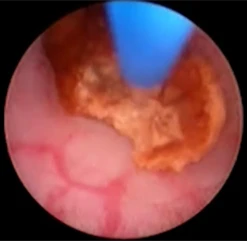

Через рабочий канал уретеропиелоскопа проводится лазерное волокно. По оптическому каналу изображение от эндоскопа передается на монитор. Волокно вплотную подводится к камню и при нажатии на педаль подаётся лазерное излучение, вследствие которого происходит деструкция камня.